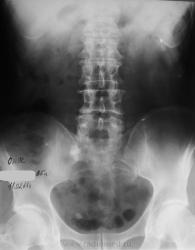

А Вы сделайте последний снимок через 12-24 часа от момента начала исследования...да с небольшим поворотом (левый бок чуть приподнять), вот тогда и посмотрим, то ли это тот "ежик" на уровне нижнего края S1 или та тень, что в малом тазу....то что камень в мочеточнике сомнений нет...но на что идти урологу...вот в чем вопрос.

Мне кажется, неоднородный камень или группа камней находится в устье правого мочеточника. Осталось неясным почему "оно" померкло на последнем снимке. Но Людмила Григорьевна умеет создать проблему на ровном месте, сама того не желая)). А в крестце вижу только очаг остеосклероза.

Виктор Григорьевич, проблема в том, что не факт, что через 12-24 часа поймаем контрастирование дистальной трети мочеточника. А КТ в нашем же отделении. Так что не стала выдумывать велосипед. Пациент получил диск, поедет в Тверь дробить руду

Петрович, Вы правы, но уже обжегшись, дую на кости - а вдруг там каменюка, а я за костные дела принимаю...